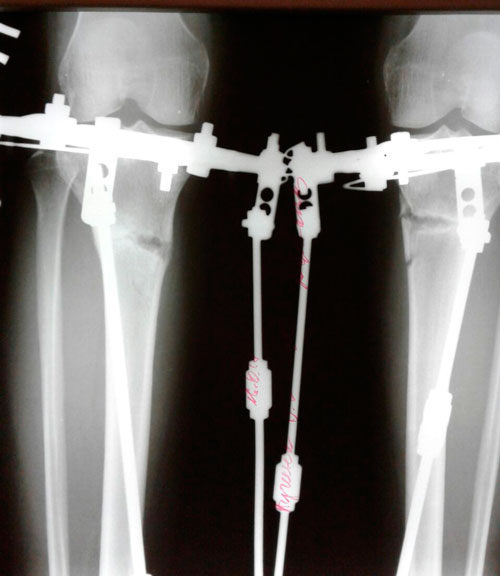

Дата операции - 11.07.2017г.

Дата снятия аппаратов 16.10.2017г.

Срок лечения 95 дней.